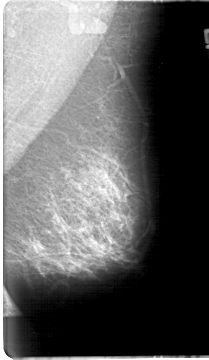

D_4067_1.RIGHT_CC

LEFT_CC LINES 5266 PIXELS_PER_LINE 2551 BITS_PER_PIXEL 12 RESOLUTION 43.5 NON_OVERLAY